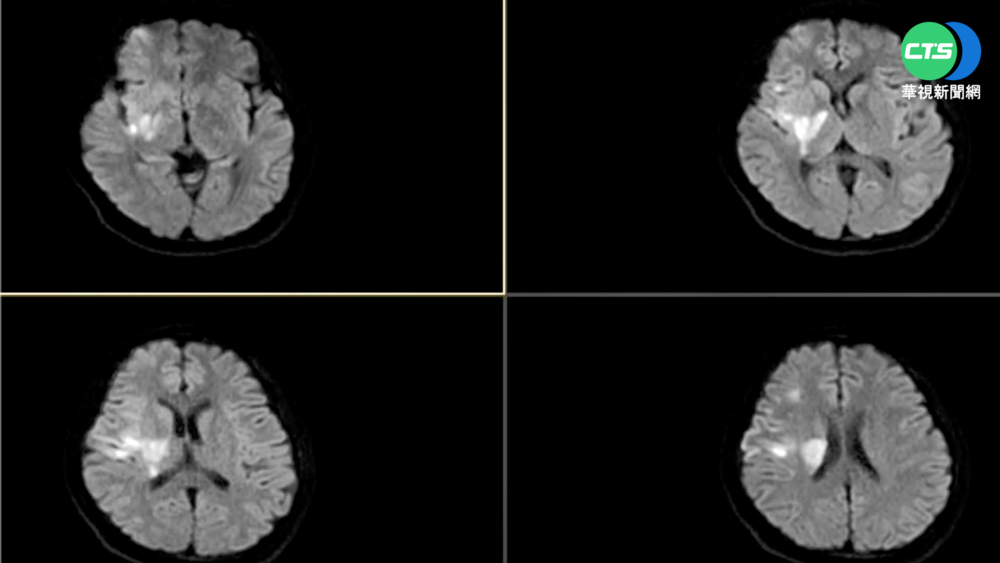

目前1歲的小俊,已經長得頭好壯壯,活動力旺盛,去年他剛出生1個月14天,出現頭部右側腫脹、食慾下降、嘔吐的症狀,醫師診斷,小俊顱骨內長了1顆5公分血管瘤,還壓迫到腦幹,讓爸爸媽媽相當緊張,小俊父親說:「就是一定很擔心啊,做切片做出來是良性的,看到是良性的,心就比較放了一半。」

院方考量,直接開顱切除腫瘤,可能造成嬰兒無法承受的出血,於是決定先使用藥物讓腫瘤縮小,再用導管進行腫瘤血管栓塞,中榮兒童神經外科主任周育誠說:「那就是血管瘤栓塞加上後續的,2個月的藥物治療控制之後,讓這腫瘤縮小,縮小之後再分階段進行開顱手術。」小俊手術後,經過1年追蹤,恢復狀況良好,醫師表示,嬰兒血管瘤好發於頸部,大約占50%,而長在顱骨內相當罕見,也是院方治療過年紀最小的個案,醫護人員運用複合手術室的技術,減少患者和家屬的壓力,讓小朋友得到最好的治療。